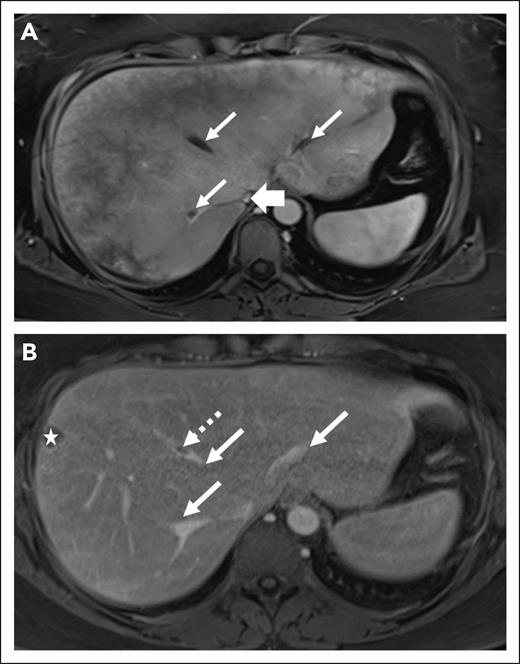

Recurrence of TEs under anticoagulants was noted in only 1 case receiving enoxaparin and 3 cases receiving warfarin, of whom 1 was found to have subtherapeutic (eg, <2) international normalized ratio levels at the time of TE recurrence. While on anticoagulation, 7 patients (5 on warfarin, and 2 on DOACs) experienced bleeding. Among them, the 2 patients on DOACs experienced an acute rectal hemorrhage but had additional bleeding risk factors (1 was on concomitant clopidogrel treatment, and the other had an additional diagnosis of ulcerative colitis). No thrombotic recurrence was observed in all 19 patients treated with DOACs at a median observation of 17.1 months (8.9-45). Because of achievement of adequate control of the manifestations of the underlying disease and considering patient choice, a discontinuation of anticoagulation was attempted in 14 patients, without any TE recurrence at a median time of 51.4 months (29.9-86.8). Of note is that radiologic studies were performed to follow-up TEs according to standard guidelines for thrombosis management outside of PNH diagnosis,34 and were deemed helpful in guiding treatment discontinuation in the absence of active hemolysis and stable disease parameters (Figure 3).

Radiologic features of thrombosis at diagnosis and follow-up of a 45-year-old woman with PNH. (A) Axial postcontrast VIBE MRI of a 45-year-old woman demonstrates heterogeneous enhancement of the liver. There is bland thrombus in 3 hepatic veins (thin arrows) and decreased IVC caliber without discrete thrombus (thick arrow). (B) After treatment, axial postcontrast VIBE image demonstrates significantly decreased thrombus burden from the prior (thin arrows) with persistent thrombus within middle hepatic vein (dashed arrow). The star indicates an incidental cyst in the liver periphery.